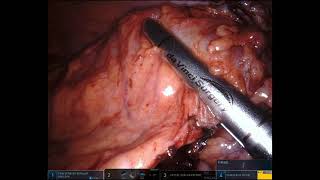

Port positions for Robotic LAR and ISR video

Port positions for Robotic LAR and ISR

Trocar Placement Robotic Left/Sigmoid Colectomy Intra-Corporeal anvil placement - Robotic LAR

Intra-Corporeal anvil placement - Robotic LAR